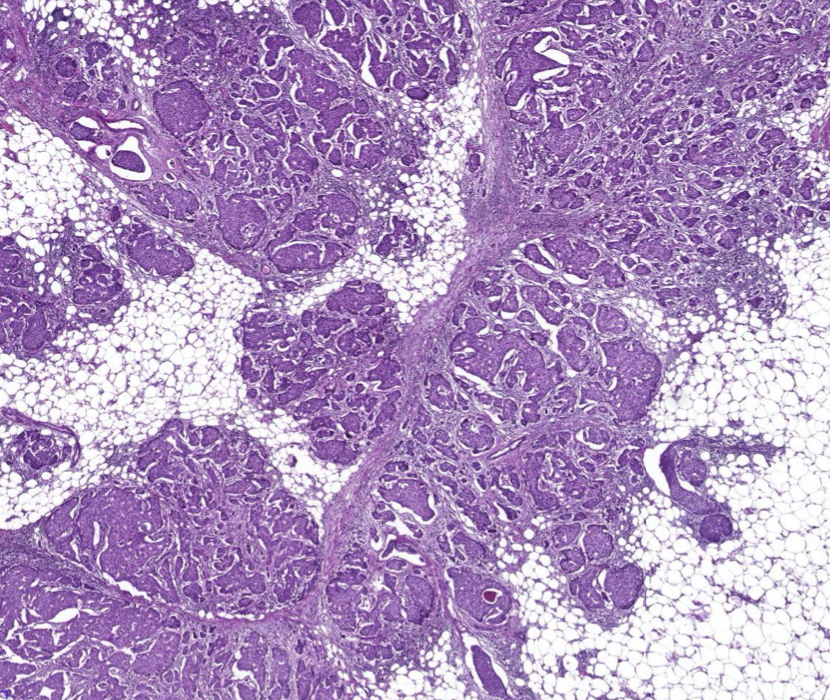

Diagnose?

Adenokarzinom des gastroösophagealen Übergangs = Barettkarzinom

Viel häufiger als Plattenepithel-CA, wird immer irregulärer je höhergradig und tieferreichender der Tumor ist, Dysplasie ist Vorstufe und Notwendigkeit zur Therapie